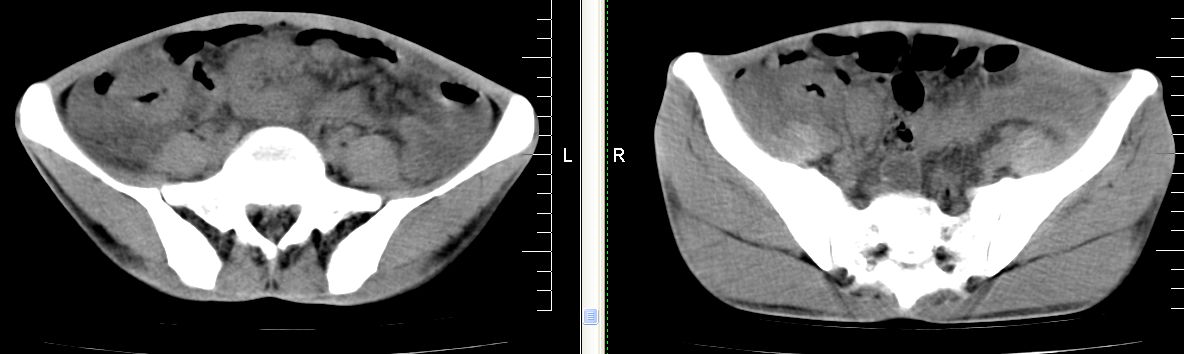

m 29 肺tb患者,目前诉下腹疼痛 t39度 腹韧,有压痛,可触及3x4cm包块

脾脏多发低密度灶,肠系膜及腹膜后见多发大小不等结节状影,右结肠旁沟见低密度影,结合病史考虑:脾结核,肠系膜及腹膜后淋巴结结核,少量腹水。

脾脏多发低密度灶,左侧肾上腺见块状病灶,密度不均,盲肠升结肠肠壁明显增厚,左下腹似可见肠壁增厚,肠系膜及腹膜后见多发大小不等结节状影,右结肠旁沟见低密度影,1淋巴瘤可能大,2结合病史考虑:脾结核,左侧肾上腺结核,肠系膜及腹膜后淋巴结结核,少量腹水待除外,

考虑脾结核及腹腔结核感染,阑尾区结核脓肿不排除